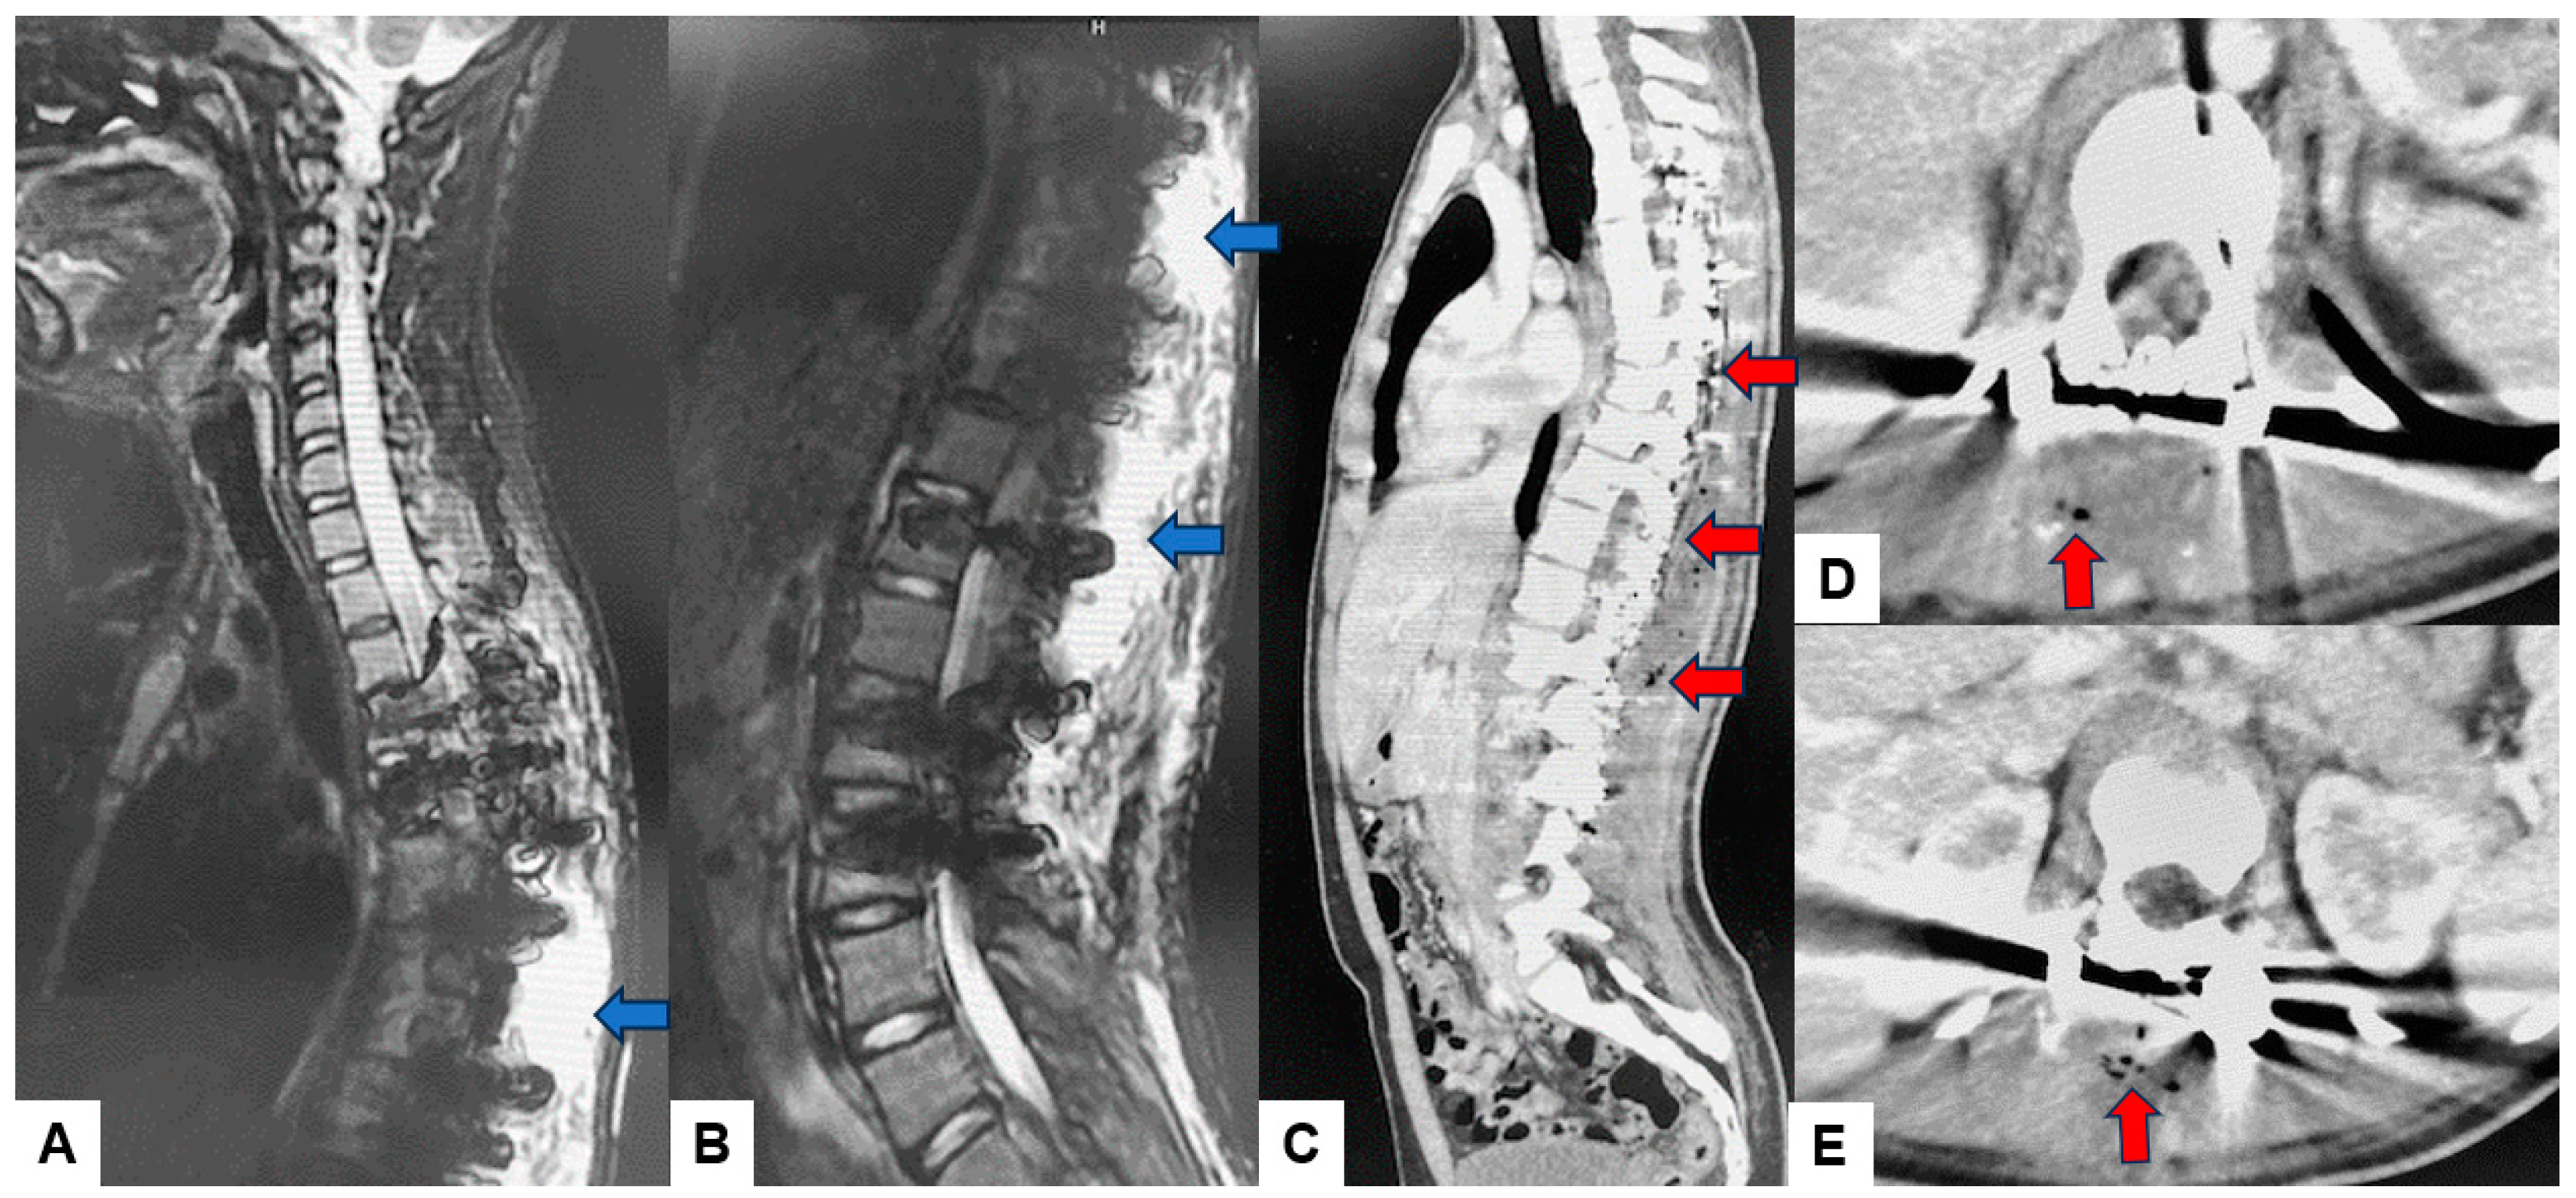

It is important to note that in our patient sample, no infections were observed in cases involving anterior approaches. This may be attributed to the minimal use of monopolar coagulation and reduced tissue disruption typically associated with anterior approaches. Additionally, our study reinforces the idea that certain types of surgeries, particularly multi-segmental fusions and scoliosis surgeries, may carry a higher risk of SSIs due to their complexity and longer operative times. Figure 3 and Figure 4 represent an example of a case undertaken at our institution for adolescent idiopathic scoliosis, in which the main surgical parameters played a major part in this scenario, and the extensive approach and long operative times resulting in SSI [13,16]. The correlation between extended surgical time and specific pathogens underlines the importance of surgical efficiency and robust perioperative management to mitigate infection risks in spine surgery. In a retrospective meta-analysis undertaken by Zhuo et al. with 22,475 patients, the evidence showed that posterior approaches had double the incidence (5% vs. 2.3%) over anterior approaches, and minimally invasive surgery had a much lower rate of infection (1.5% vs. 3.8%) [17].

Previous reports have emphasized both CE MRIs and CTs can help to identify the underlying microorganisms and differentiate the most frequent subtypes [18]. These image modalities can provide important features to diagnose infectious conditions and to avoid unnecessary biopsy and anti-bacterium treatments. Figure 3 and Figure 4 present the SSI after scoliosis correction surgery. It was a little difficult to use the MRI to evaluate SSI because of metal artifacts. However, enhanced CT revealed gas inside the abscess/effusion which is relatively specific to SSI (Figure 4).

Figure 4. 13 M, Adolescent idiopathic scoliosis, MRI and enhanced CT at postoperative Day 12. (A) Midsagittal cervicothoracic T2 weighted MR imaging, (B) Midsagittal thoracolumbar T2 weighted MR imaging, (C) Enhanced midsagittal reconstruction CT, (D) Enhanced T8 axial CT, (E) Enhanced L1 axial CT. Blue arrows indicate postoperative abscess/effusion. Red arrows revealed gas inside the abscess/effusion.